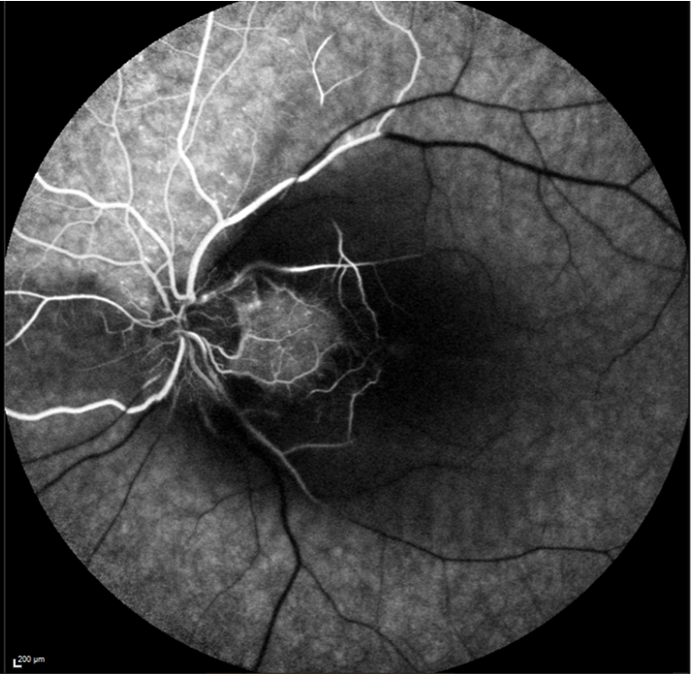

Angiographie à la fluorescéine d’un patient atteint d’OACR de l’œil gauche. Retard circulatoire du colorant visible, persistance d’une perfusion de colorant par l’artère cilio rétinienne.

L’examen doit être réalisé en urgence. Une mesure de l’acuité visuelle par l’orthoptiste est réalisée, suivie de l’instillation de collyres dans les deux yeux. La dilatation des pupilles permet à l’ophtalmologiste d’explorer le fond d’œil et de réaliser une angiographie rétinienne à la fluorescéine. Un OCT maculaire complète le bilan et met en évidence la présence d’œdème maculaire.

Sur le plan ophtalmologique, un traitement par laser sur les zones ischémiques sera discuté selon les résultats angiographiques. Les IVT d’anti VEGF peut être associées dans certains cas, pour limiter la dégénérescence des cellules ganglionnaires ou réduire un œdème de la tête du nerf optique.